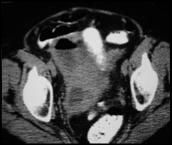

Perforated Appendicitis with right pyosalpinx and pyometra